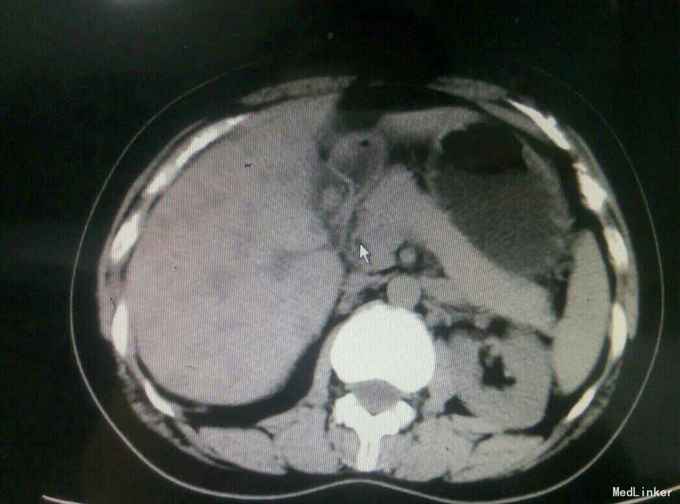

患者,女,43岁,左乳癌术后2年余,发现肝脏占位3天

查体:未及明显异常 辅助检查:腹部彩超发现肝脏多发占位,考虑转移,腹部增强CT:肝脏多发结节,考虑乳腺癌肝转移

诊断与治疗:乳腺癌术后伴肝转移,患者原病理为ER.PR阴性,Her-2高表达,术后行TE化疗、放疗以及靶向治疗,此次采取GX姑息性辅助化疗。

随访与讨论:患者入院时肝功能就偏高,也算是一个肝功能受损征相,而且彩超检查发现门静脉有癌栓形成,说明比较晚期,预后不良,所以采取姑息性辅助化疗,希望可以减轻患者病痛。当然同时也要排除其他地方转移,以采取相关治疗措施。